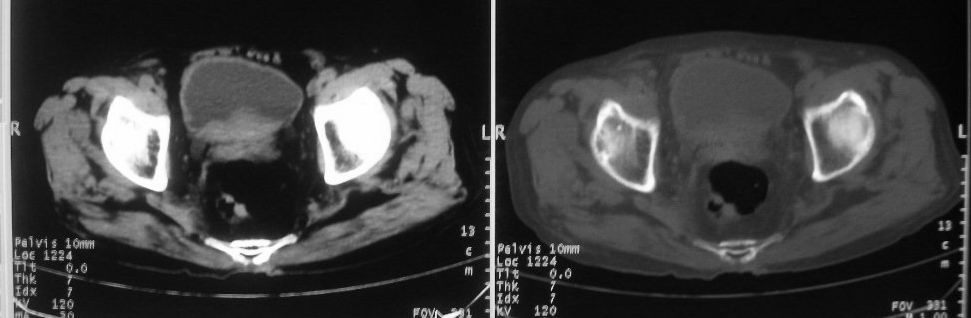

以下是引用zjzjr在2008-10-3 12:59:00的发言:[br]前列腺癌伴左髂骨\\腰椎转移可能性大.

以下是引用卜一在2008-10-3 13:40:00的发言:[br]前列腺癌!左髂骨\\腰椎转移?建议行全身骨扫描!

以下是引用深泽交通医院在2008-10-3 15:33:00的发言:[br]前列腺实性增大伴分叶状,与包膜间隙境界不清;椎体松质区间结节样密度影,考虑:前列腺癌,并椎体成骨性转移